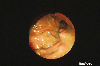

치료에 의하여 화상소견이 변화된 장결핵(1970년대의 증례)

내시경